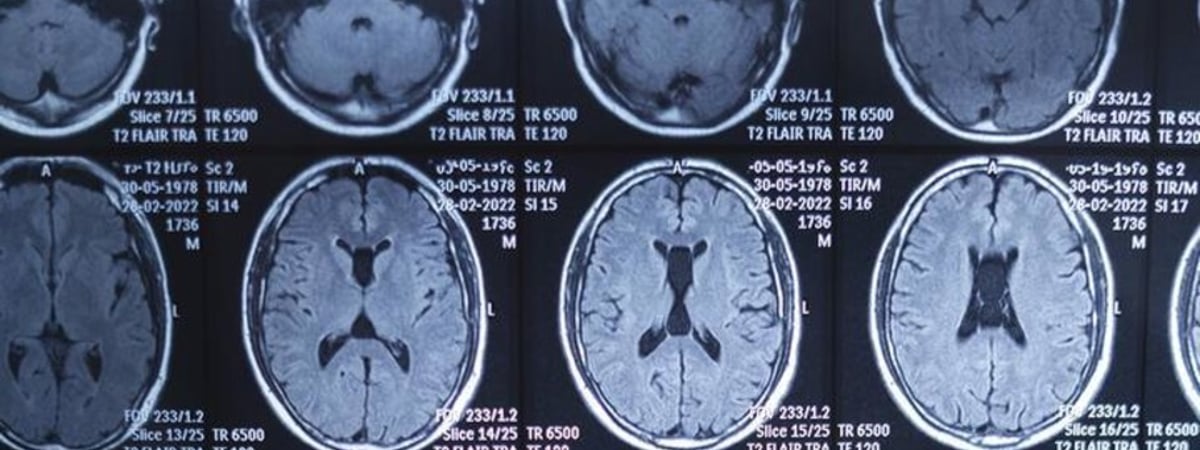

Исследователи из Питтсбургского университета обнаружили, что вирус простого герпеса первого типа может быть одной из причин развития болезни Альцгеймера. Ученые обнаружили белки вируса герпеса в образцах мозга пациентов рядом с характерными для этого заболевания скоплениями тау-белка в наиболее уязвимых участках мозга, пишет Зеркало со ссылкой на «Хайтек».

Эксперименты на лабораторных моделях человеческого мозга показали, что вирус герпеса может влиять на уровень тау-белка. Изначально это служит защитным механизмом, снижающим гибель нейронов после вирусной инфекции. Однако позже такой защитный ответ может привести к повреждению мозга.

«Наше исследование меняет представление о тау-белке как исключительно вредном факторе. Мы показали, что изначально он может быть частью иммунной защиты мозга», — заявил руководитель исследования Ор Шемеш.

Точные механизмы, через которые вирус герпеса влияет на развитие болезни Альцгеймера, пока остаются неизвестными. Ученые продолжат исследования, чтобы разработать новые методы лечения, направленные на борьбу с вирусными белками или регуляцию иммунного ответа мозга.